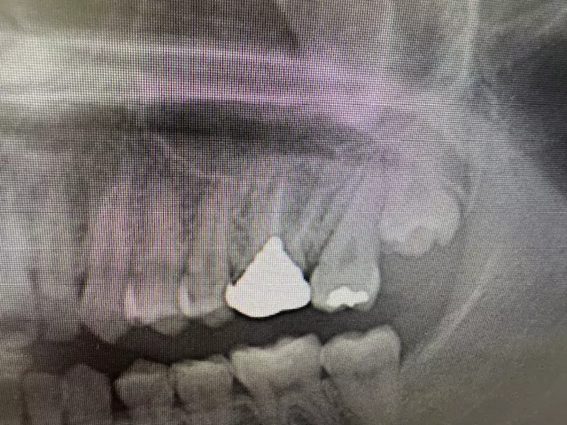

| 主訴 | 左上5番部インプラント埋入 |

| 治療内容 | 隔壁を傷つけないようドリリング後、隔壁部分も利用しつつソケットリフト。骨補填後埋入。ISQ値60 トルク値35N程度。もともと歯が無い部位にインプラント希望。 |